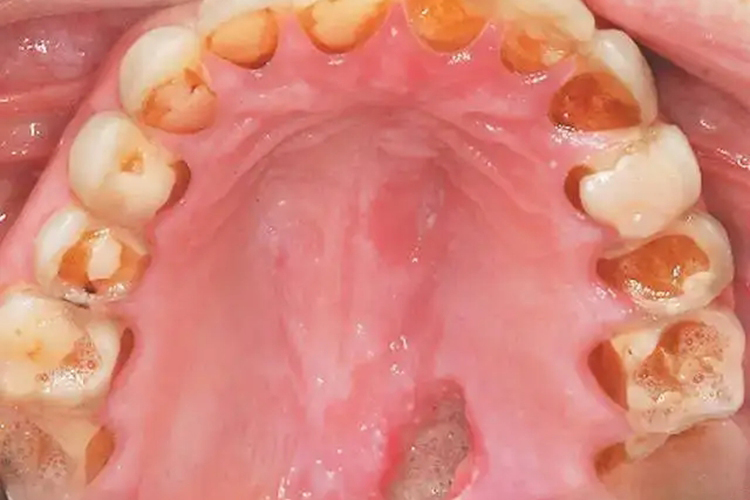

长期催吐牙齿受损腐烂是由于胃酸反流,腐蚀牙齿造成牙齿的酸蚀症,主要表现为牙齿的腭侧被腐蚀。

长期催吐牙齿受损腐烂主要表现为牙齿的腭侧被胃酸腐蚀,出现牙齿腭侧表面凹凸不平,轻者可出现沟状损害,严重者可能出现大面积深度破坏。